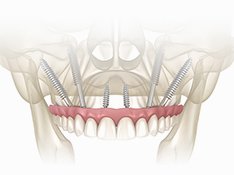

オールオン4 All-on-4

オールオン4は、4本のインプラントで上顎または下顎の人工歯列を支える方法です。従来の多数本インプラントよりも少ない本数で治療できるため、身体的負担や治療期間、費用を抑えられることが特徴です。

オールオン4では、インプラントを斜めに埋め込むことで噛む力を広く均等に分散し、最小4本のインプラントで上顎または下顎の全ての人工歯を支えることができます。日帰りで手術が可能なため、患者さまの身体的な負担も軽減され、手術当日に仮歯を装着できます。わずか1日で口元の機能と見た目が改善され、これまでの歯に関する悩みから解放されます。多くの歯を失った患者さまにとって、治療にかかる時間や費用、身体の負担を最小限に抑えながら、安定した噛み心地と自然な見た目を実現できる治療法です。